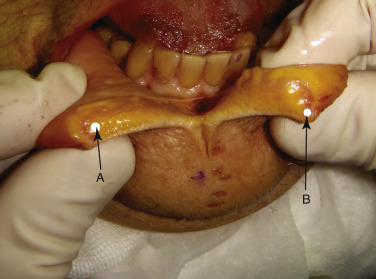

I have heard numerous high profile doctors say that “their patients don’t need supplemental anesthesia.” If that is true it is because the patient doesn’t know better. Although some surgeons employ local anesthetic blocks, I do not use them, because they are more difficult and less dependable than infiltration techniques and numb large areas of the face for hours. Using an infiltration I refer to as the “mini block” technique, a series of injections is performed across the upper and/or lower sulcus. A 1-mL syringe with a 33-gauge needle is used with 2% lidocaine and 1 : 100,000 epinephrine. The epinephrine can be omitted to reduce the longevity of the anesthesia. Lidocaine in 0.2-mL aliquots is injected just above the upper sulcus ( Fig. 10.5 ) and just below the lower sulcus ( Fig. 10.6 ). This is generally performed in four to five areas from the canine tooth on one side to the canine tooth on the other side. The patient is then allowed 5 min for the anesthetic to take action. The local anesthetic will affect lip animation and this is another important reason for marking the patient prior to local anesthesia so landmarks are not lost or distorted. In addition, some of the wrinkles that existed with animation may not be visible if the lip is not moving normally.